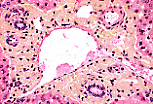

肝血窦

光镜(MO)下,固定良好的标本中无法观察到狄氏间隙; 可通过细长的细胞核识别内皮细胞,内皮细胞紧密贴合肝细胞的血管面。

狄氏间隙内存在纤细的网状纤维网,可通过银染法显示。

除内皮细胞外,血窦内还可见体积更大的细胞,细胞核形态不规则、有时弯曲,即枯否细胞(Kupffer细胞)。

给大鼠静脉注射墨汁后,其肝脏标本可显示枯否细胞的吞噬功能: 墨汁颗粒出现在枯否细胞的胞质中,而不在内皮细胞内。